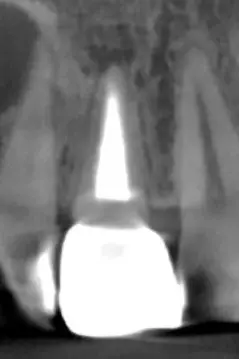

Запалення навколо кореня зуба

Запальний процес у кістковій тканині — наслідок інфекції в кореневих каналах. У таких випадках повторне ендодонтичне лікування дає можливість зберегти зуб і його функцію.

Проведено ревізію та повне перелікування каналів із застосуванням сучасної оптики, ретельної механічної й медикаментозної обробки та герметичного пломбування.

Результат: усунули інфекцію та створили умови для відновлення кісткової тканини.